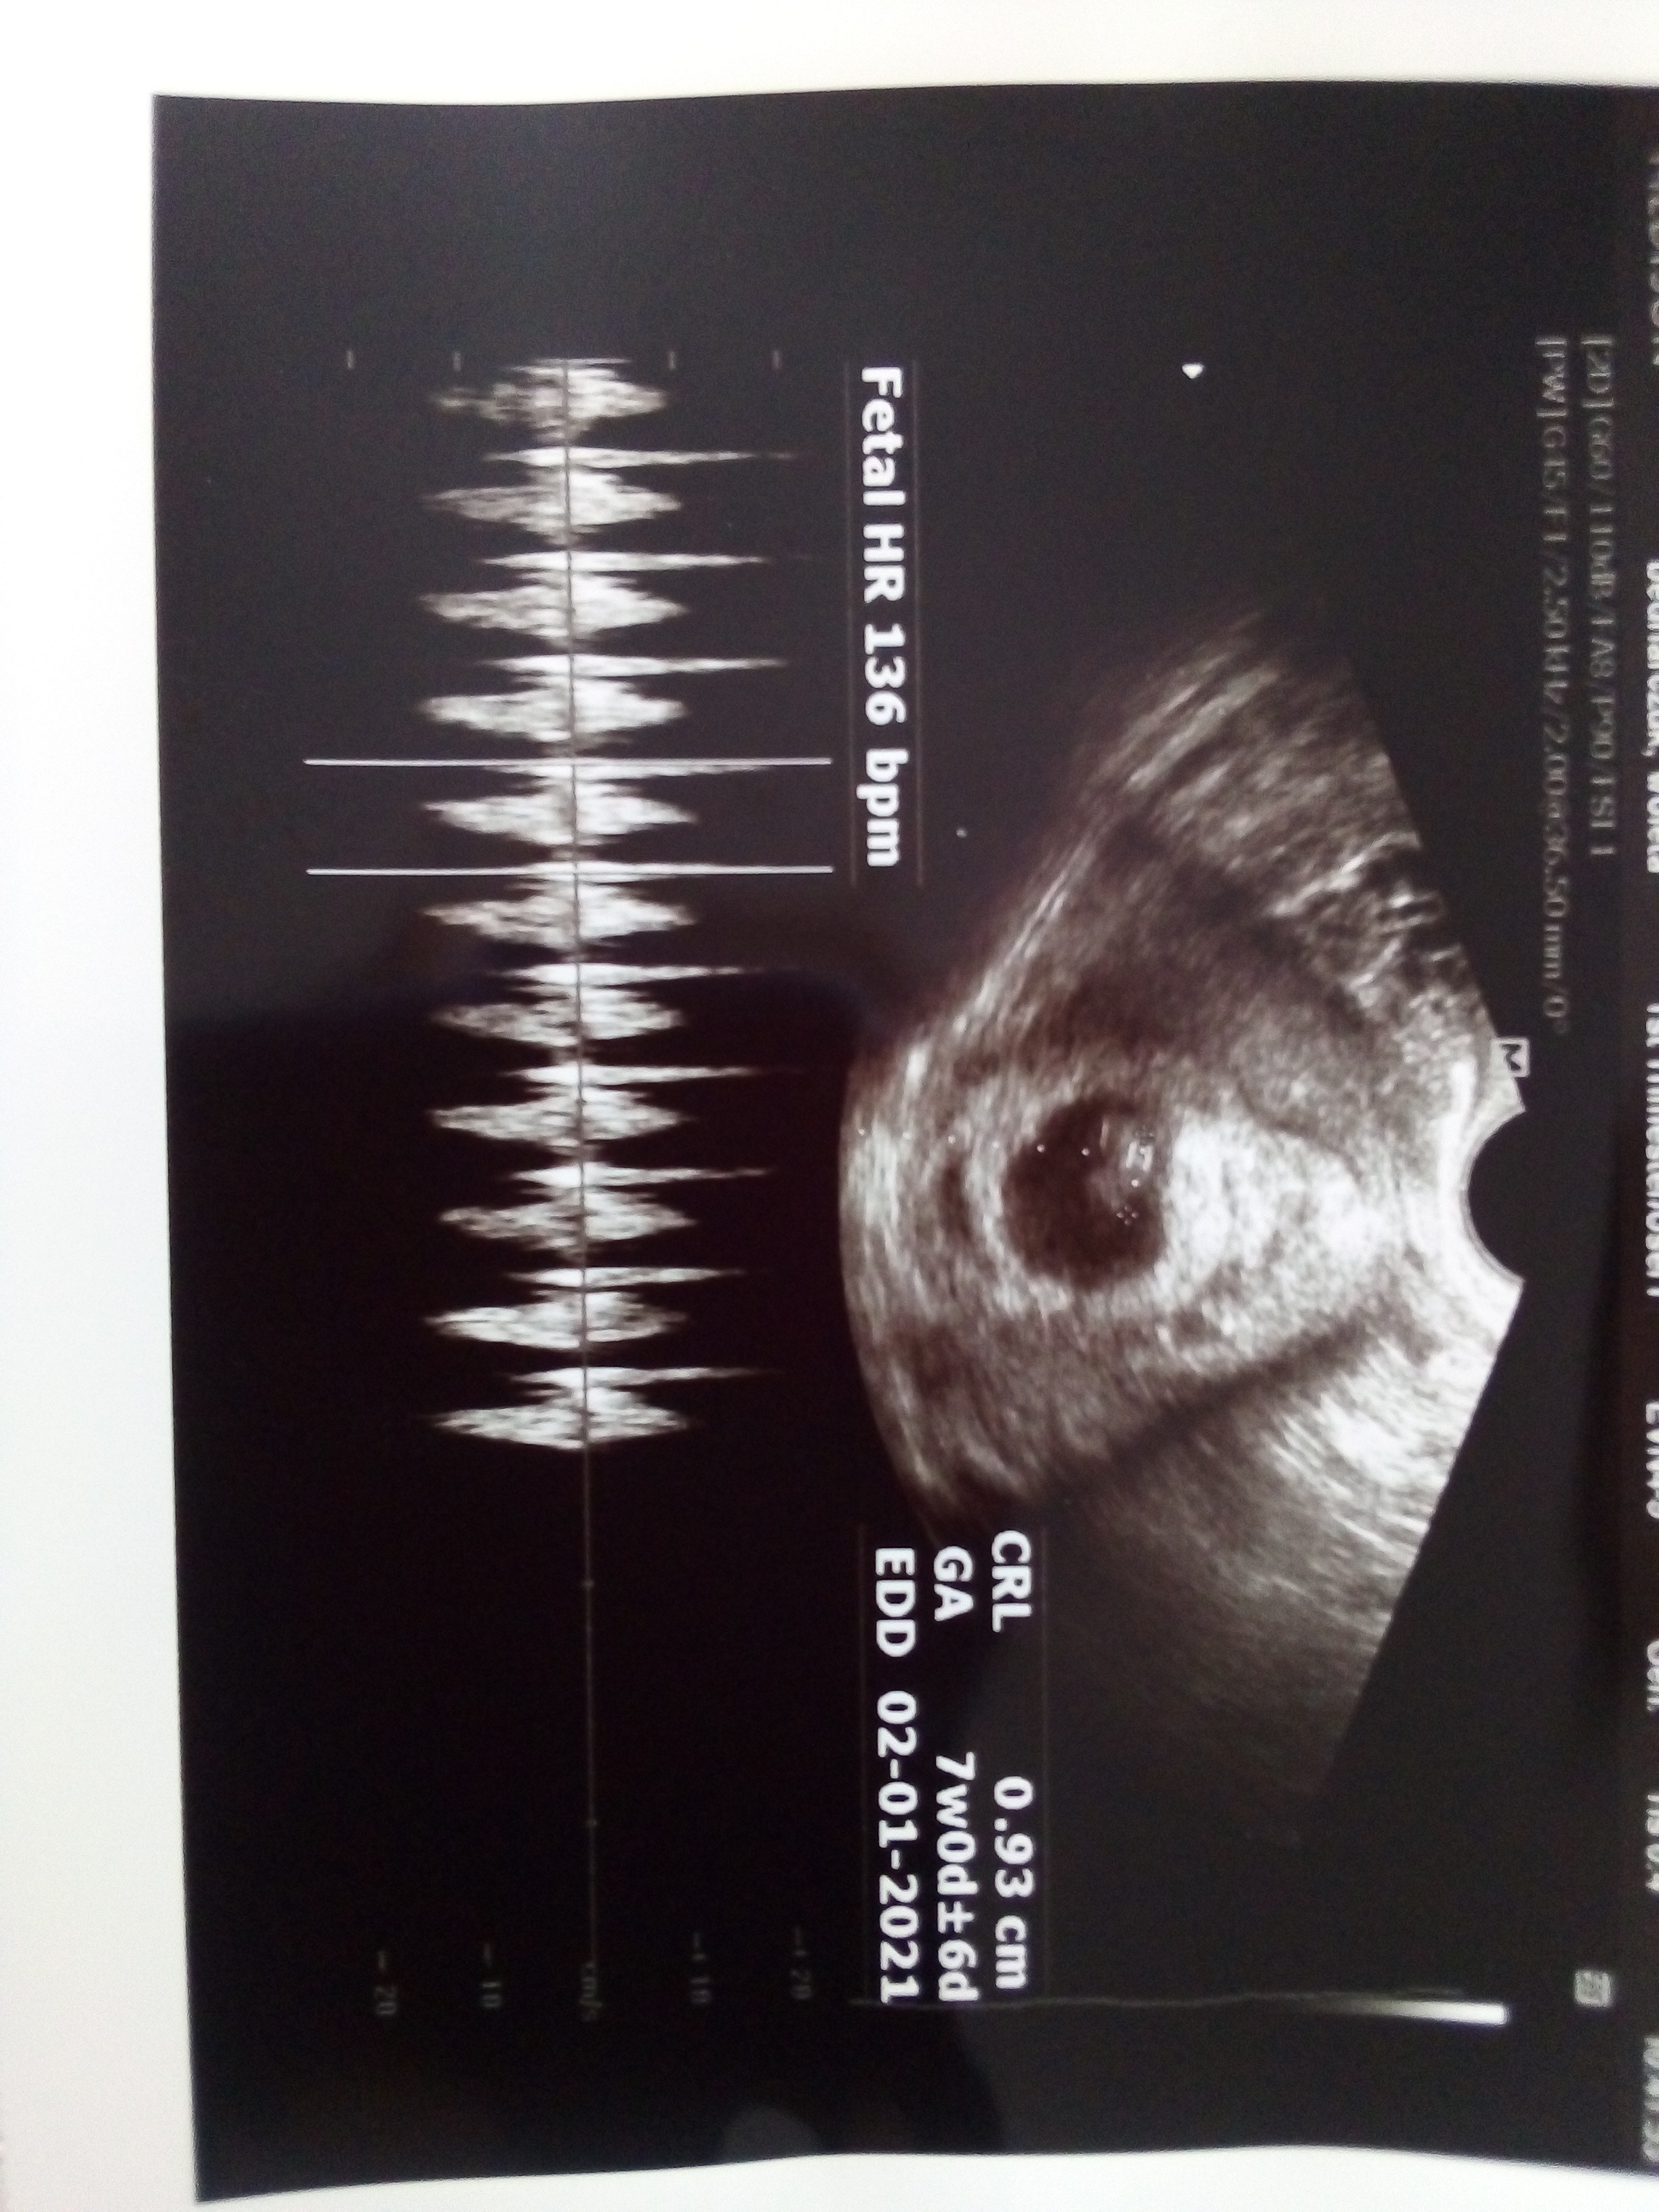

U mnie w środę była wizyta i 6+1. Był już dzidziuś 0,39 cm i serduszko ❤ Kolejna wizyta na 10.06. Już się nie mogę doczekać

U mnie w środę była wizyta i 6+1. Był już dzidziuś 0,39 cm i serduszko ❤ Kolejna wizyta na 10.06. Już się nie mogę doczekać![]()